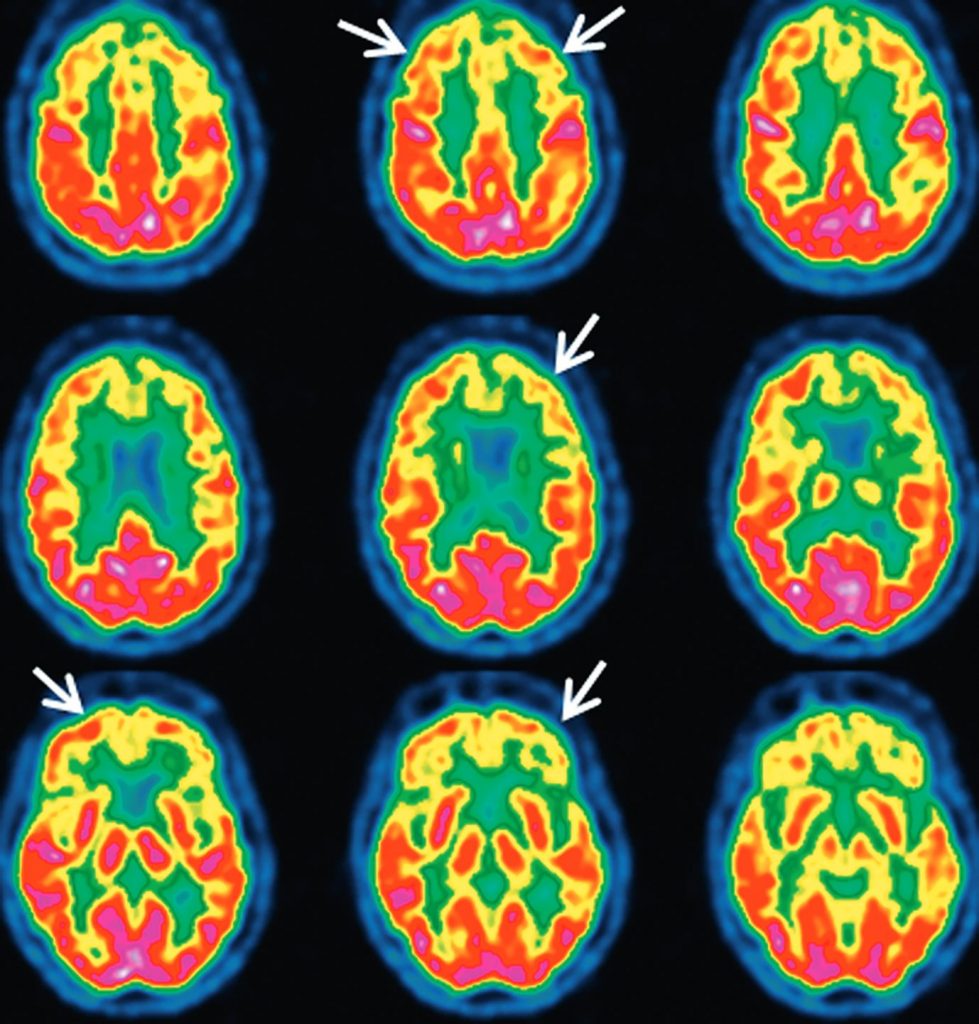

La TEP au 18FDG met en évidence un hypométabolisme et une hypoperfusion prédominant au niveau du cortex associatif pariétotemporal et des structures temporales internes (figure 53.5), à la différence de la démence frontotemporale, pour laquelle les anomalies touchent le cortex frontal et les pôles temporaux (figure 53.6).

Fig. 53.5. TEP au 18FDG en coupes axiales.

Métabolisme cortical normal (A). Maladie d’Alzheimer au stade de démence (B) : hypométabolisme sévère du cortex pariéto-temporo-occipital bilatéral (flèches) et des structures amygdalo-hippocampiques (étoiles). Maladie d’Alzheimer au stade prodromal (C) : hypométabolisme cortical modéré se limitant au cortex pariétotemporal gauche (flèches). Hypométabolisme temporal interne bilatéral.

Source : CERF, CNEBMN, 2022.